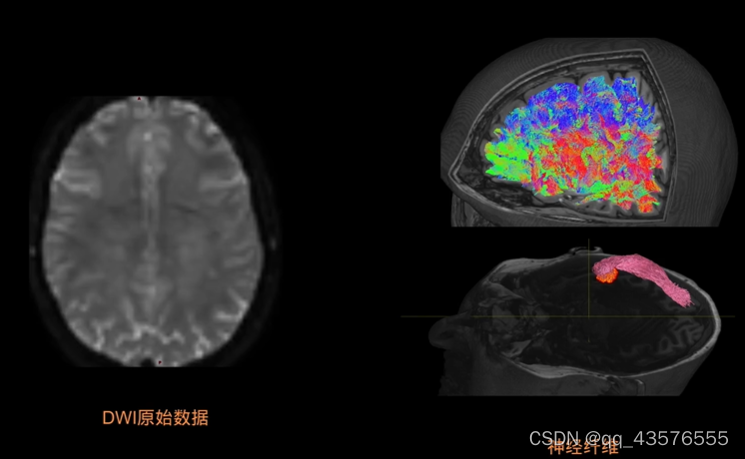

大脑的内部有灰质和白质,白质的主要成分就是神经,水分子的弥散方向倾向于沿着神经细胞轴突的走向,也就是沿着神经的方向,通过测定的弥散加权像(DWI)就可以推断出大脑内部白质神经纤维束的走向

tckgen: [100%] 367099 seeds, 259465 streamlines, 200000 selected将得到的追踪像 .tck文件和结构像T1w放在mrview中打开,选择Tractography选项,就得到了对比图如下,可以选择不同的切面

基于兴趣区的追踪与之类似,改变某些参数即可,下图为视觉纤维束